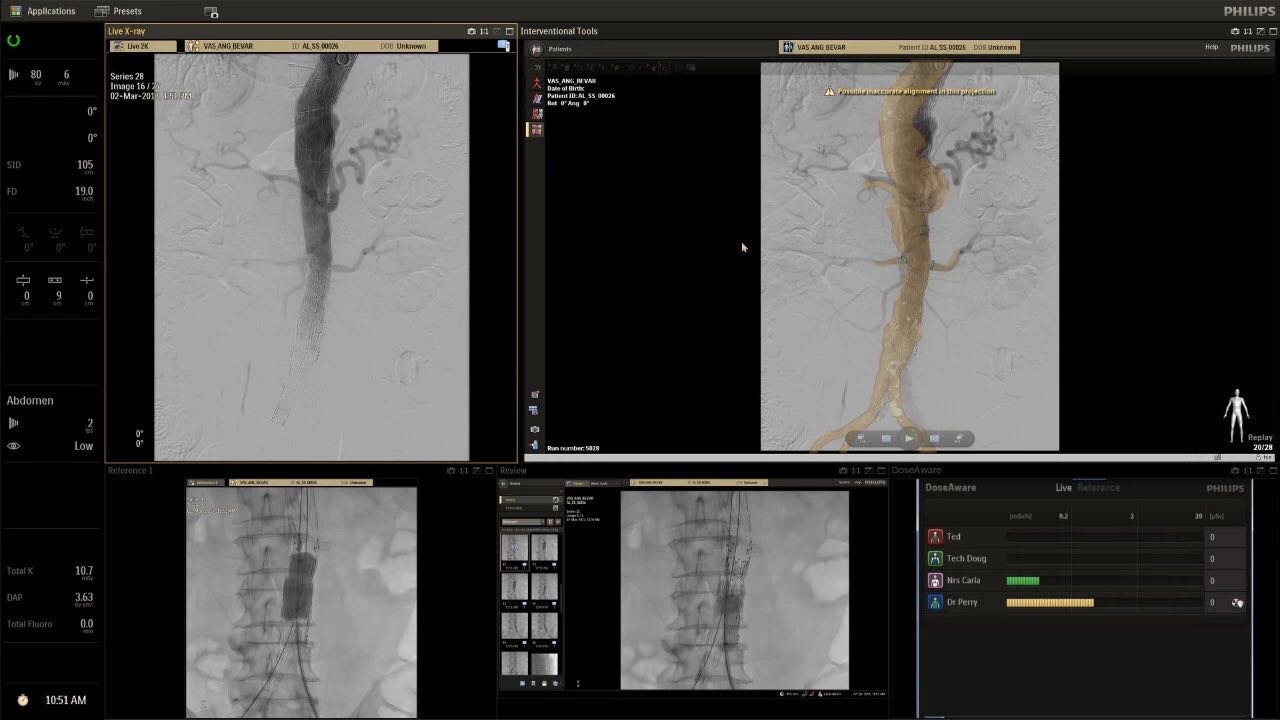

在日益復雜的干預期間,臨床醫(yī)生需要快速、輕松地可視化關鍵解剖結構并確定手術過程中患者的變化。2019年1月17日,飛利浦宣布推出采用FlexArm的Azurion 7 C20,旨在提高圖像引導程序的定位靈活性。

帶有FlexArm的Azurion 7 C20 包含一系列創(chuàng)新技術,使臨床醫(yī)生可以更輕松地在整個患者身上進行二維和三維成像。當臨床醫(yī)生移動系統(tǒng)時,圖像光束自動保持與患者的對準,允許更一致的可視化并使他們能夠將注意力集中在治療上。

(FlexArm C型臂可以沿著工作臺的兩側提供偏心成像。這允許醫(yī)生在左臂或右臂上進行徑向進入病例,完全或部分伸展,而無需移動患者或樞轉桌子。X射線束與手臂保持對齊,以促進其整個長度的平滑導航,而無需進行持續(xù)調整。)

飛利浦表示,采用FlexArm設計的Azurion 7 C20可提供卓越的靈活性和直觀的控制。該系統(tǒng)由智能運動引擎驅動,可在八個不同的軸上移動,所有這些軸均由其單個“Axsys”控制器控制。臨床醫(yī)生的模擬測試表明,該系統(tǒng)有可能顯著減少患者,工作人員和設備的重新定位,從而改善微創(chuàng)手術的可及性,包括通過患者手腕進入身體的手術(橈動脈入路),并降低患者的風險。無意中拔出電線和管子,以及節(jié)省大量時間。該系統(tǒng)非常適合混合手術室(OR),可滿足一個房間內的多種專業(yè)需求,例如手術和血管內手術的組合。

FlexArm在不少于8軸的情況下旋轉,從而創(chuàng)建幾乎無限的靈活性來執(zhí)行成像,從頭部到腳部在左側和右側進行2D和3D可視化。圖像光束保持與患者對齊,允許在旋轉或角度期間更好地可視化解剖結構。使用Axsys運動控制系統(tǒng)輕松操作支架。